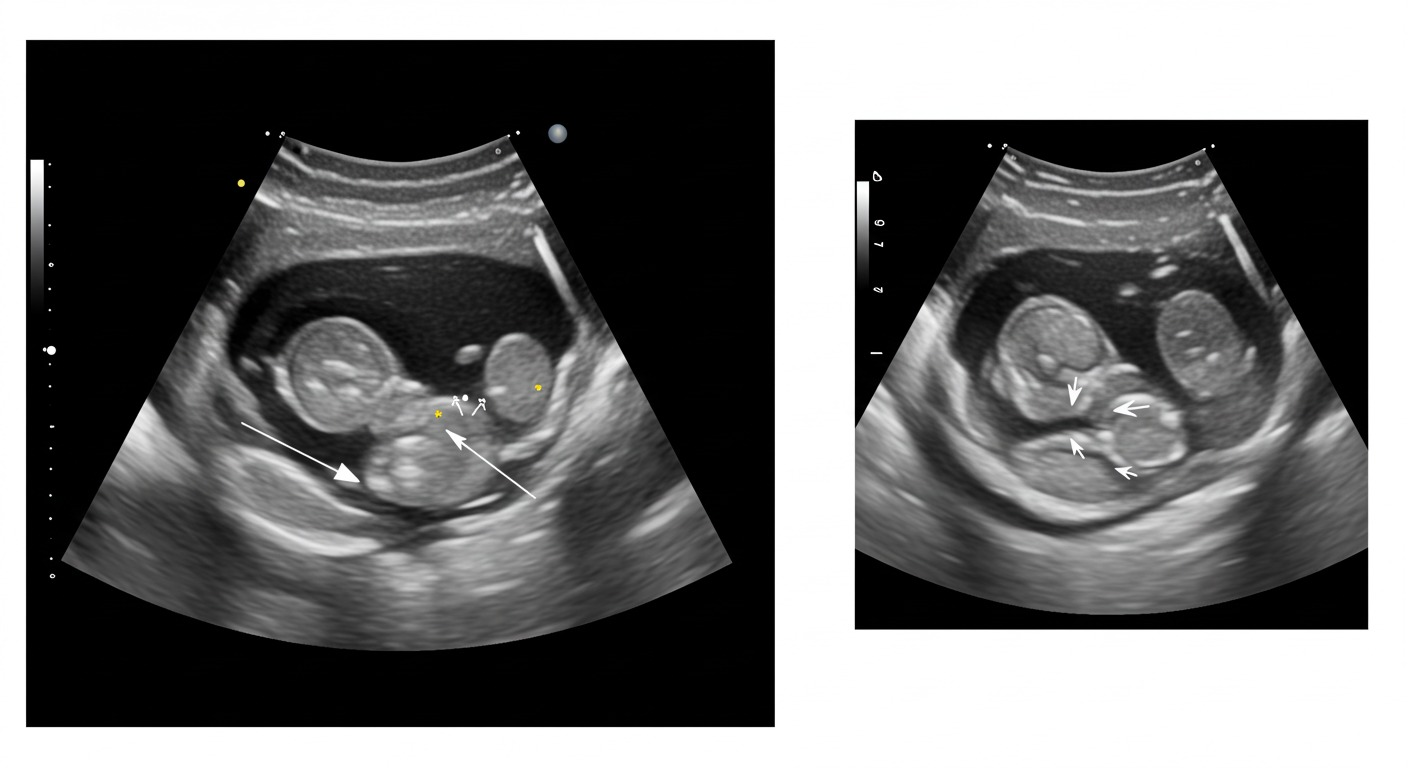

تشوّهات الأجنّة هي اضطرابات تحدث عندما يتطوّر الجنين بشكل غير طبيعي أثناء الحمل، وقد تُؤثّر في جزء من الجسم أو في الجسم كله. وتُعدّ هذه التشوّهات من القضايا الصحيّة المهمّة التي تستدعي اهتمام الأطباء والآباء، إذ قد تنعكس سلبًا على صحّة الجنين ومستقبله

تشوّهات الأجنّة هي اضطرابات تحدث أثناء نمو الجنين، مما يؤدي إلى تطور غير طبيعي في جزء من الجسم أو الجسم كله. تُعتبر هذه التشوّهات من القضايا الصحيّة المهمّة التي تستدعي انتباه الأطباء والأهل، إذ قد تؤثر على صحة الجنين ومستقبله.